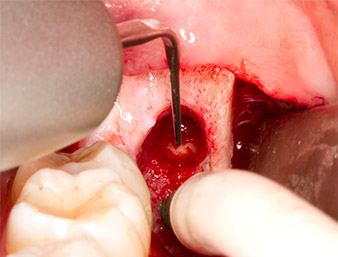

Nach Leitungs- und Lokalanästhesie wurde das Operationsfeld für einen bukkal-retromolaren Zugang weichgewebig eröffnet und dargestellt (Abb. 3).

sulkuläre Schnitt

Abb. 3: Der sulkuläre Schnitt beginnt Mitte des Zahnes 36, mit distaler Verlängerung am aufsteigenden Ast.